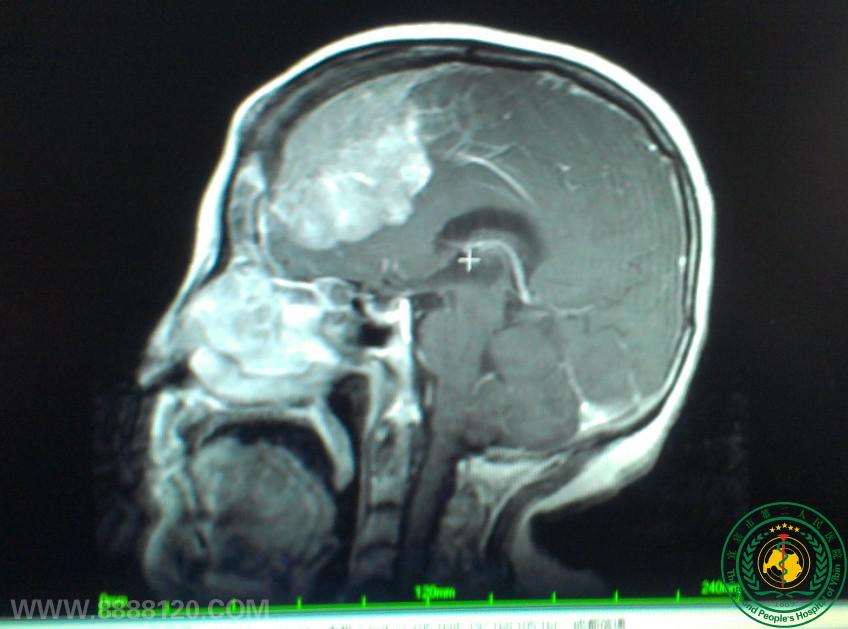

我科顺利完成颅内巨大脑膜瘤一例

我科顺利完成颅内巨大脑膜瘤一例5840